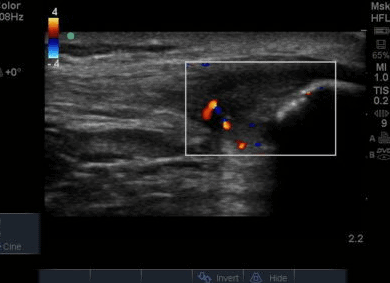

Chẩn đoán viêm gân bánh chè dựa vào thăm khám lâm sàng kết hợp với các phương tiện chẩn đoán hình ảnh. Trong đó, Siêu âm và MRI là hai phương pháp phổ biến nhất.

Hình ảnh viêm gân bánh chè, gân dày giảm âm, tăng tưới máu trên siêu âm Doppler

Vai trò của siêu âm trong chẩn đoán viêm gân bánh chè

Siêu âm được lựa chọn là phương pháp đầu tay nhờ những ưu điểm vượt trội:

Hình ảnh trên siêu âm: * Gân bánh chè dày lên, giảm âm (đen hơn bình thường).